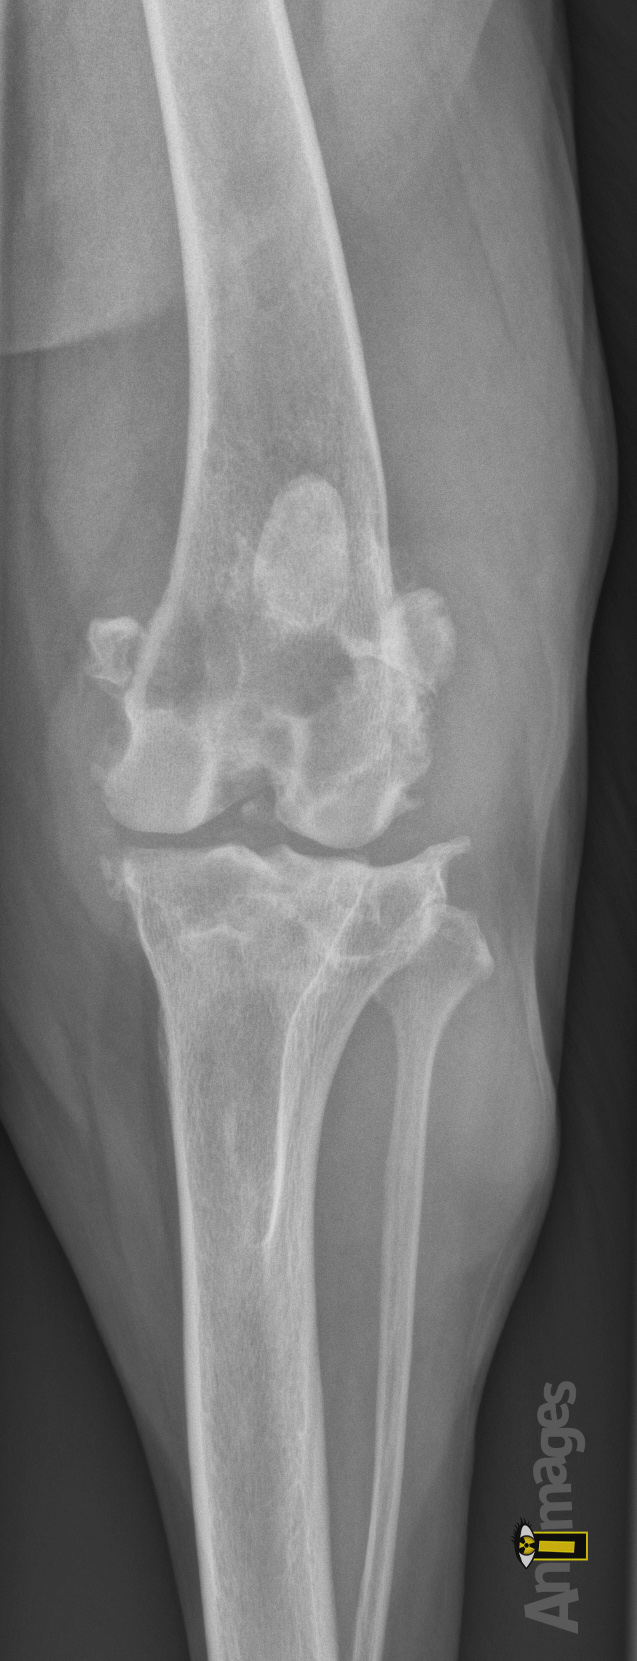

Craniocaudale